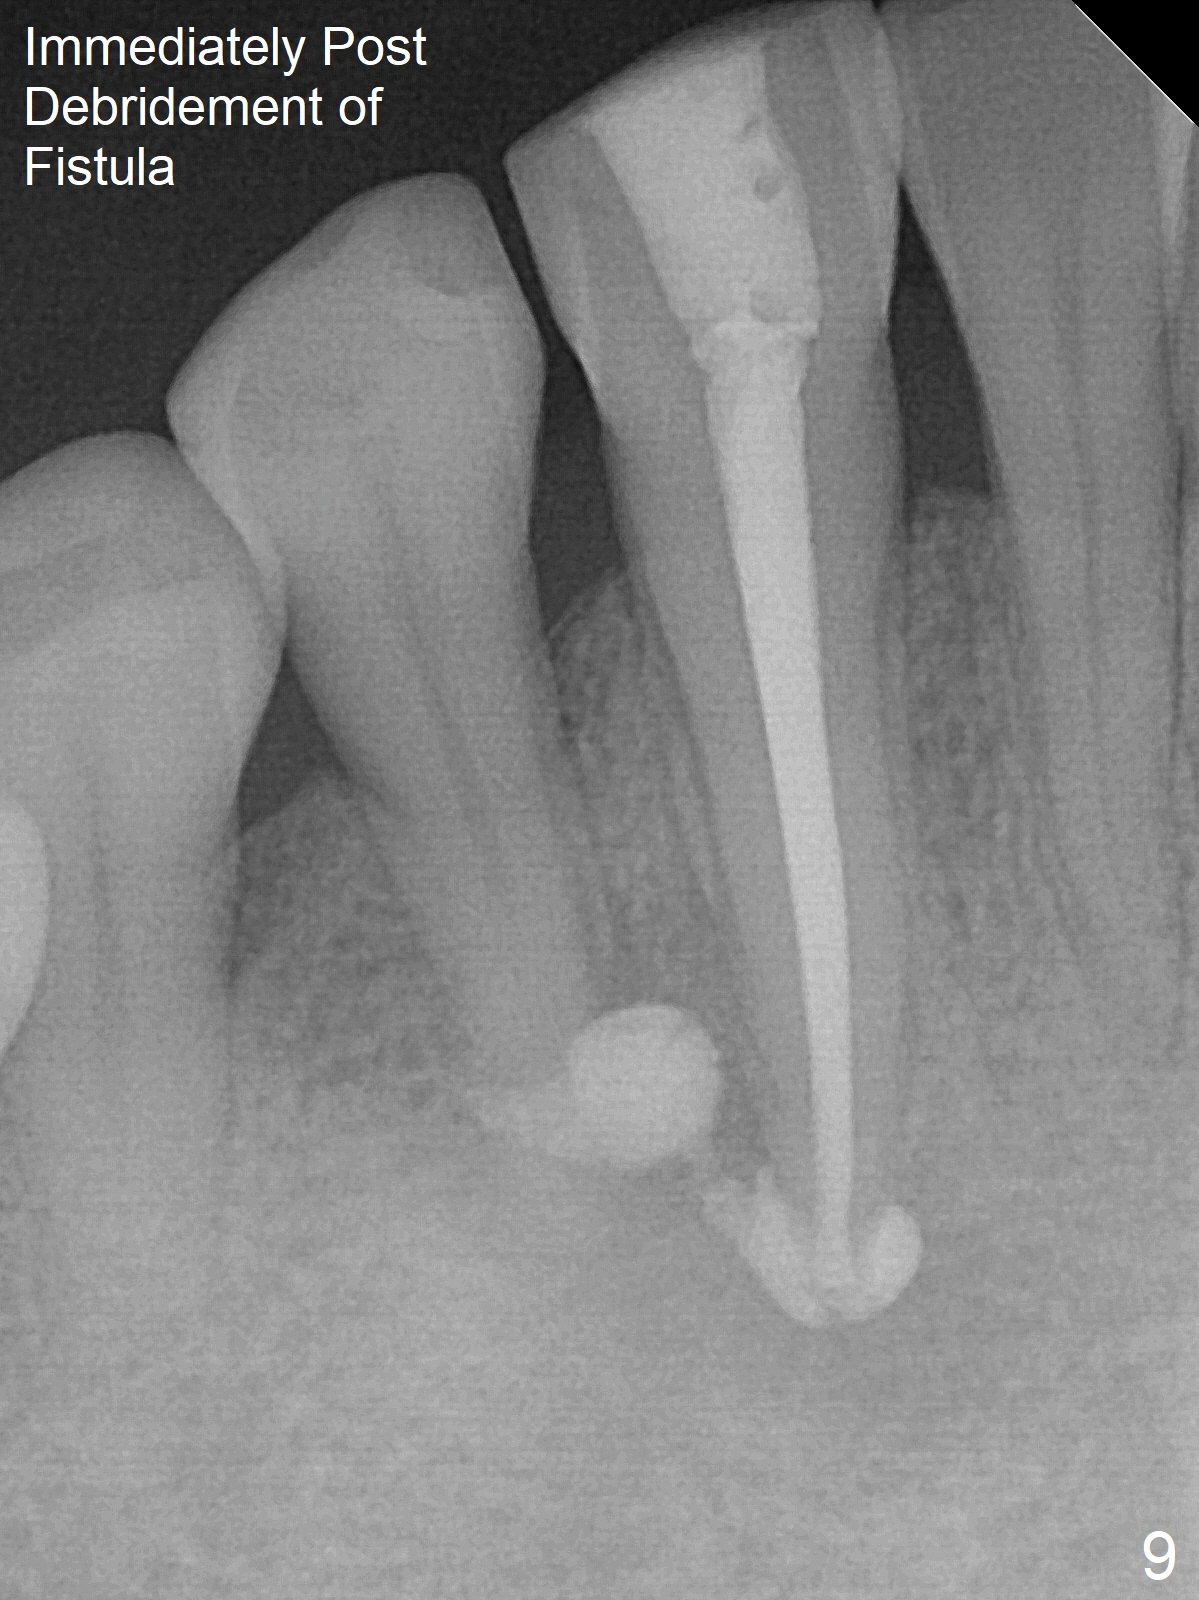

The patient reports that the fistula disappears after initial RCT at #27, but it seems to re-appear 1 month post canal debridement (Fig.5 >). After repeated debridement with #40 hand file at 23 mm, apply Endo Sequence BioCeramic Sealer and insert GT 40/.08 master cone with black carrier (Fig.6). One hour later, the patient returns with re-appearance of the fistula (Fig.7). Following local anesthesia, poking the fistula leads to sealer escape (Fig.8). After debridement of the fistula until the bone, PA is retaken (Fig.9). A crown was made in China; mesial radiolucency starts (Fig.10). The tooth remains asymptomatic 1 year 5 months postop (Fig.11). There is a lingual fistula with enlarged mesial radiolucency 2 years 3 months postop (Fig.12-14).